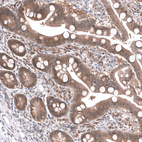

Immunohistochemistry analysis in human testis and skeletal muscle tissues using HPA007667 antibody. Corresponding MAPK13 RNA-seq data are presented for the same tissues.